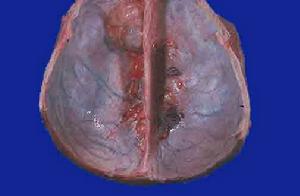

除了合併神經纖維瘤病被認為是與細胞遺傳學有關外,一般多發腦膜瘤的病因尚不清楚腦膜瘤術後再出現的多發腦膜瘤,可以用瘤細胞隨腦脊液播散解釋,但無法解釋原發多發的腦膜瘤。Borovich等觀察14例大腦凸面腦膜瘤發現在腫瘤四周的硬腦膜上有散在多處的病灶,這些病灶在硬腦膜層之間叢生呈串珠狀。任何病理類型都可出現在多發腦膜瘤,同一病人可以出現不同病理類型的腦膜瘤。

多發性腦膜瘤1.顱內出血或血腫 與術中止血不仔細有關,隨著手術技巧的提高,此併發症已較少發生創面仔細止血,關顱前反覆沖洗,即可減少或避免術後顱內出血